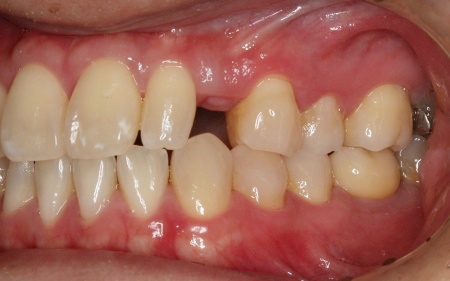

拝見したところ、左上の糸切り歯が欠損していました。

デメリット:外科的な処置を伴う。今回は歯を入れるためのスペースがやや狭かったため、矯正治療でスペースを確保してから行う必要があり、治療期間が約2年と長くなる

②失った歯の手前の前歯1本を支えとして、2本分の被せ物を装着する片側固定ブリッジ

それぞれのメリット・デメリットをご説明したところ、患者様は当初①のインプラント治療をご希望でしたが、矯正治療の併用や治療期間の長さへの不安から、最終的に②の片側固定ブリッジを選択されました。

また今回はブリッジを装着するためのスペースがやや不足しているため、手前の歯を小さめに削って必要なスペースを確保する必要があることも併せて説明しています。